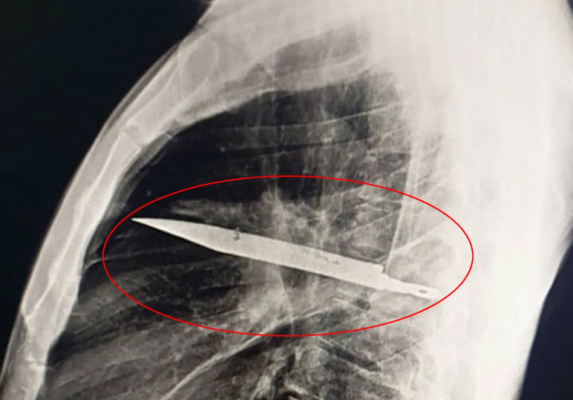

Недавно 44-летний мужчина обратился в медучреждение с жалобами на боль и гнойные выделения из правого соска. Врачи провели ему рентген-исследование и были ошеломлены. Оказалось, что в груди пациента застряло длинное лезвие ножа. Узнав об этом, мужчина вспомнил, что восемь лет назад в ходе ссоры получил несколько ножевых ранений, после чего прошел лечение и считал, что все зажило.

Однако нож, вошедший внутрь через правую лопатку, так и остался внутри и лишь чудом не повредил жизненно важные органы. Гной, который появлялся недавно, образовался из-за омертвевших тканей вокруг лезвия. Операция по извлечению инородного тела прошла успешно. Мужчина провел сутки в реанимации, а затем еще 10 дней в общей палате. Восстановление прошло без осложнений.